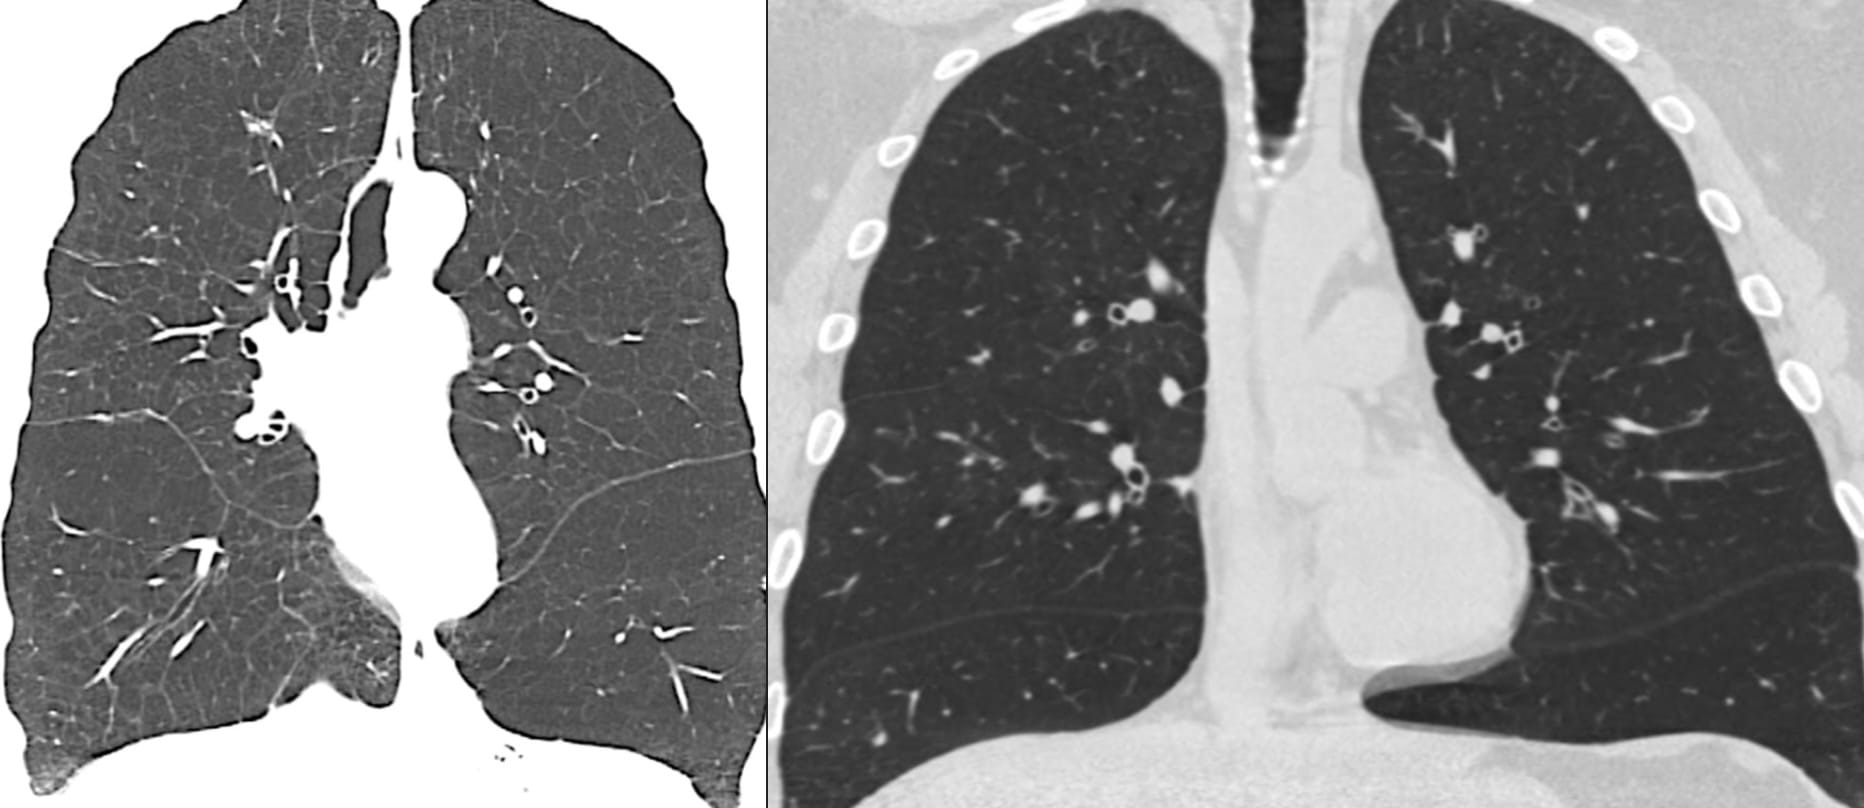

Airway-dominant phenotype

Emphysema-dominant phenotype

Mixed phenotype

We can make these distinctions on CT.